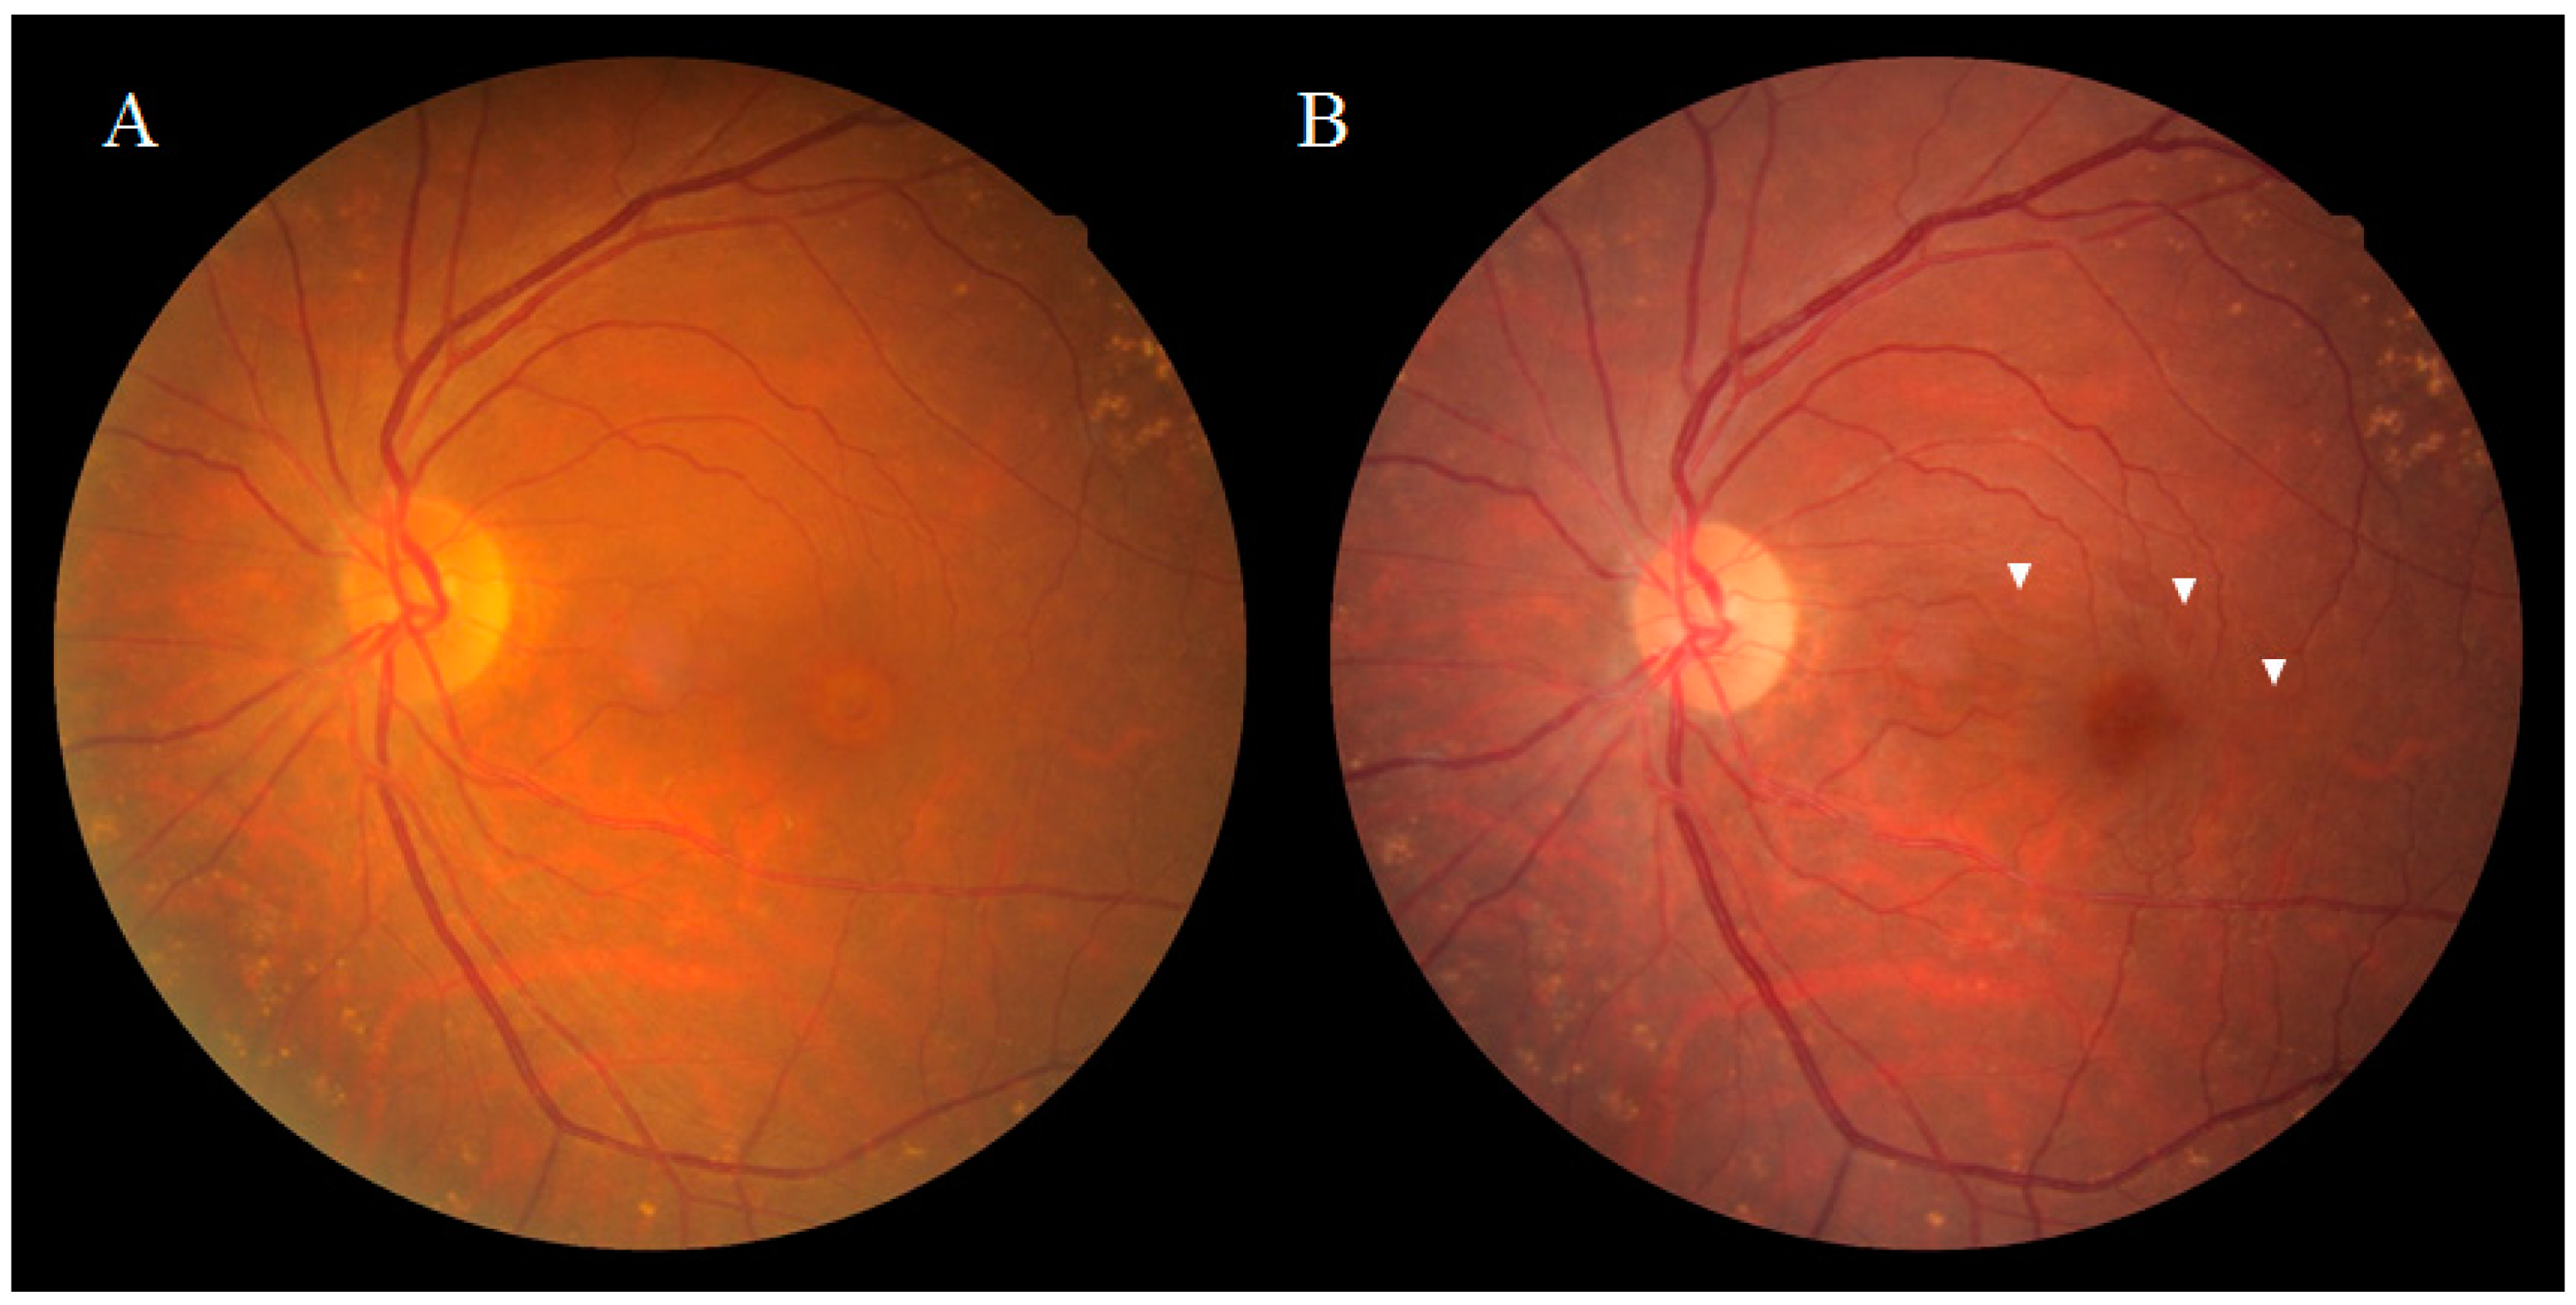

2. Anatomical Features of DONFL Appearance

2.1. DONFL Appearance and Visual Function